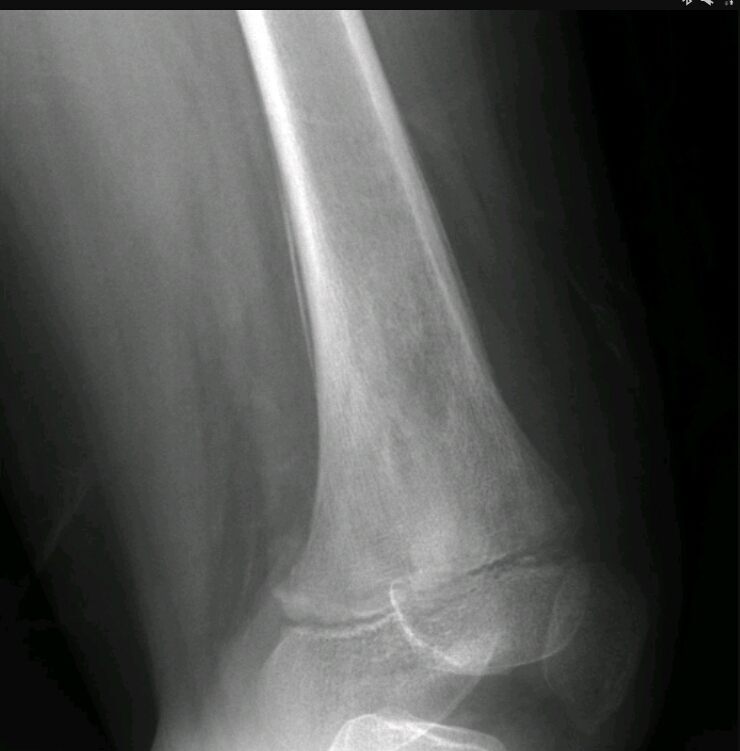

Onion skin appearance in the diaphysis of the femur

Ewing’s sarcoma